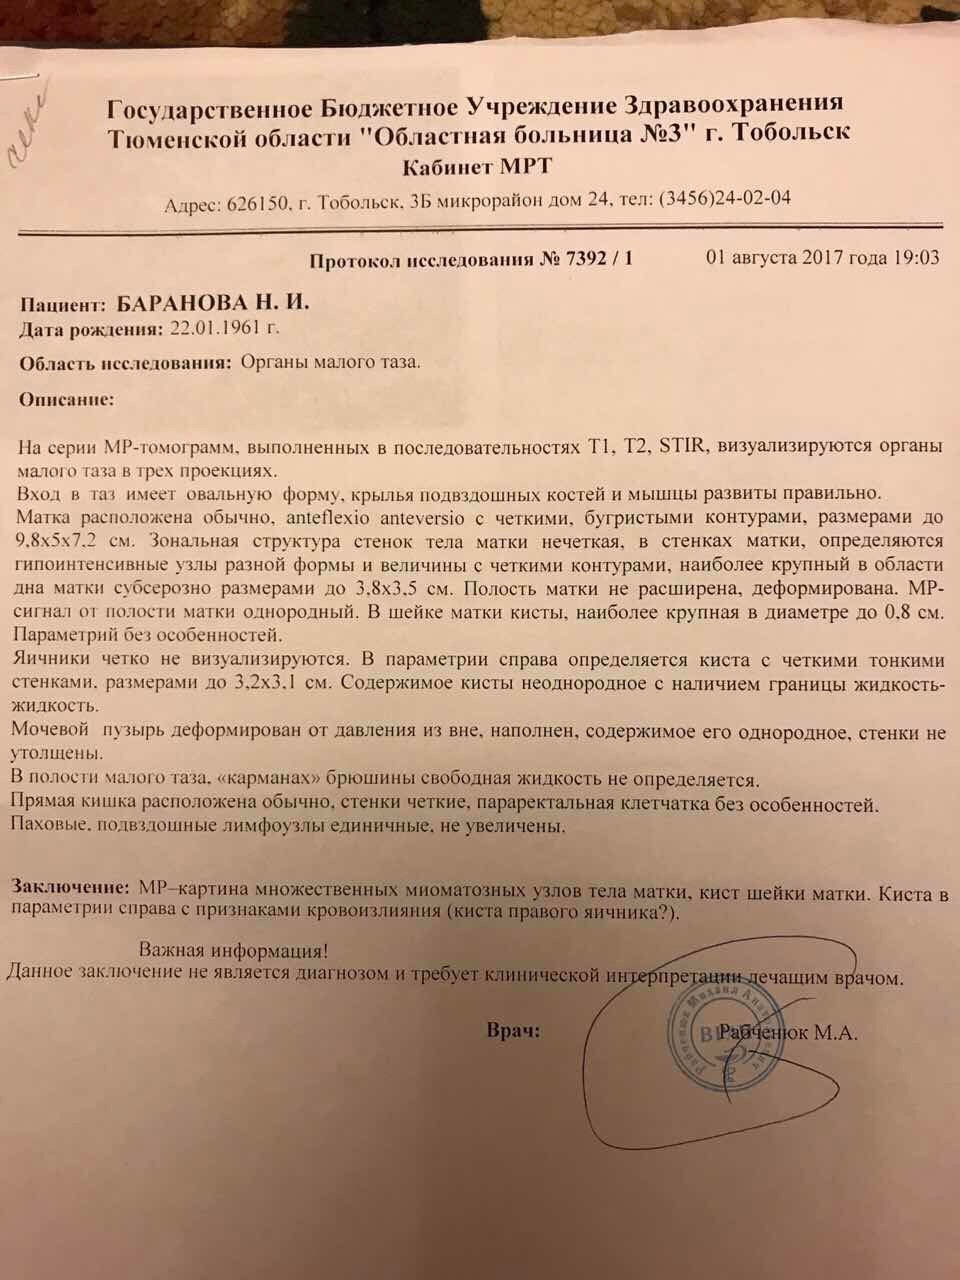

Злокачественная опухоль на матке заключение

Примеры фото МРТ малого таза у женщин

Ниже представлены примеры фотографий МРТ малого таза у женщин, позволяющие увидеть, как выглядят снимки и какие изменения могут быть обнаружены специалистами.